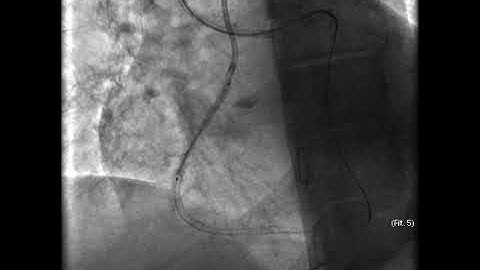

[COMPLEX PCI 2020] E-Training Session IV: CTO-PCI